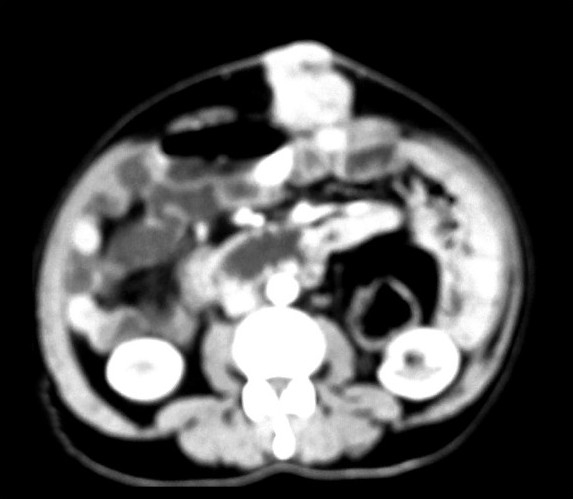

He had recurrence of abdominal pain in December 2008. This time he was found to have a mass in the supra umbilical region at the site of laparotomy incision scar [Figure 1]. He also had a complaint of painful bleeding piles. Clinical examination revealed left side axillary lymph node enlargement, a parietal anterior abdominal wall soft tissue mass and perianal nodules with bleeding piles. CT scan revealed a parietal mass in anterior abdominal wall [Figure 2]. He underwent biopsy from the abdominal mass and was found to have recurrent Non-hodgkins lymphoma. The histopathology was suggestive of a lymphoblastoid pattern. Immunohistochemistry was performed at this stage and was found to have Cyclin D1, CD5, CD19, CD20, and CD22 positivity. Bone marrow examination was positive for disease. He was thus diagnosed as having recurrent Non-hodgkin’s lymphoma of mantle cell variety with stage IV disease and was started on second line single agent Lenalidomide. He was found to be unresponsive to treatment and progressed even while on chemotherapy. He was subsequently taken up for palliative radiotherapy to the abdominal wall mass and perianal region, which yielded significant symptomatic relief. He is currently under follow-up and being considered for Bortezomib and rituximab based therapy.

| Figure 2 CT scan showing parietal mass in anterior abdominal wall